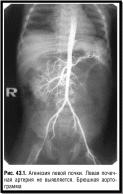

Диагностика: Подозрение на солитарную почку возникает при пальпации увеличенной безболезненной почки, однако диагноз можно поставить лишь на основании углубленного рентгеноурологического исследования (экскреторной урографии, цистоскопии, почечной ангиографии).

При аортографии появление контраста на стороне агенезии отсутствует (рис. 43.1). Цистоскопия выявляет отсутствие соответствующего устья мочеточника и гемиатрофию мочепузырного треугольника. Ангиография указывает на отсутствие почечной артерии.